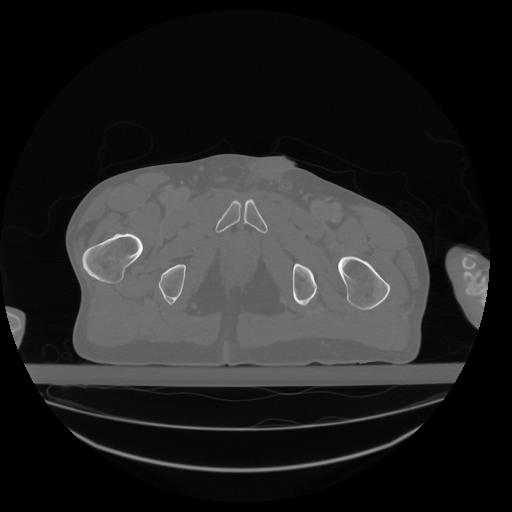

34 CUERPO,CE,Vol,1.0,CUERPO,,